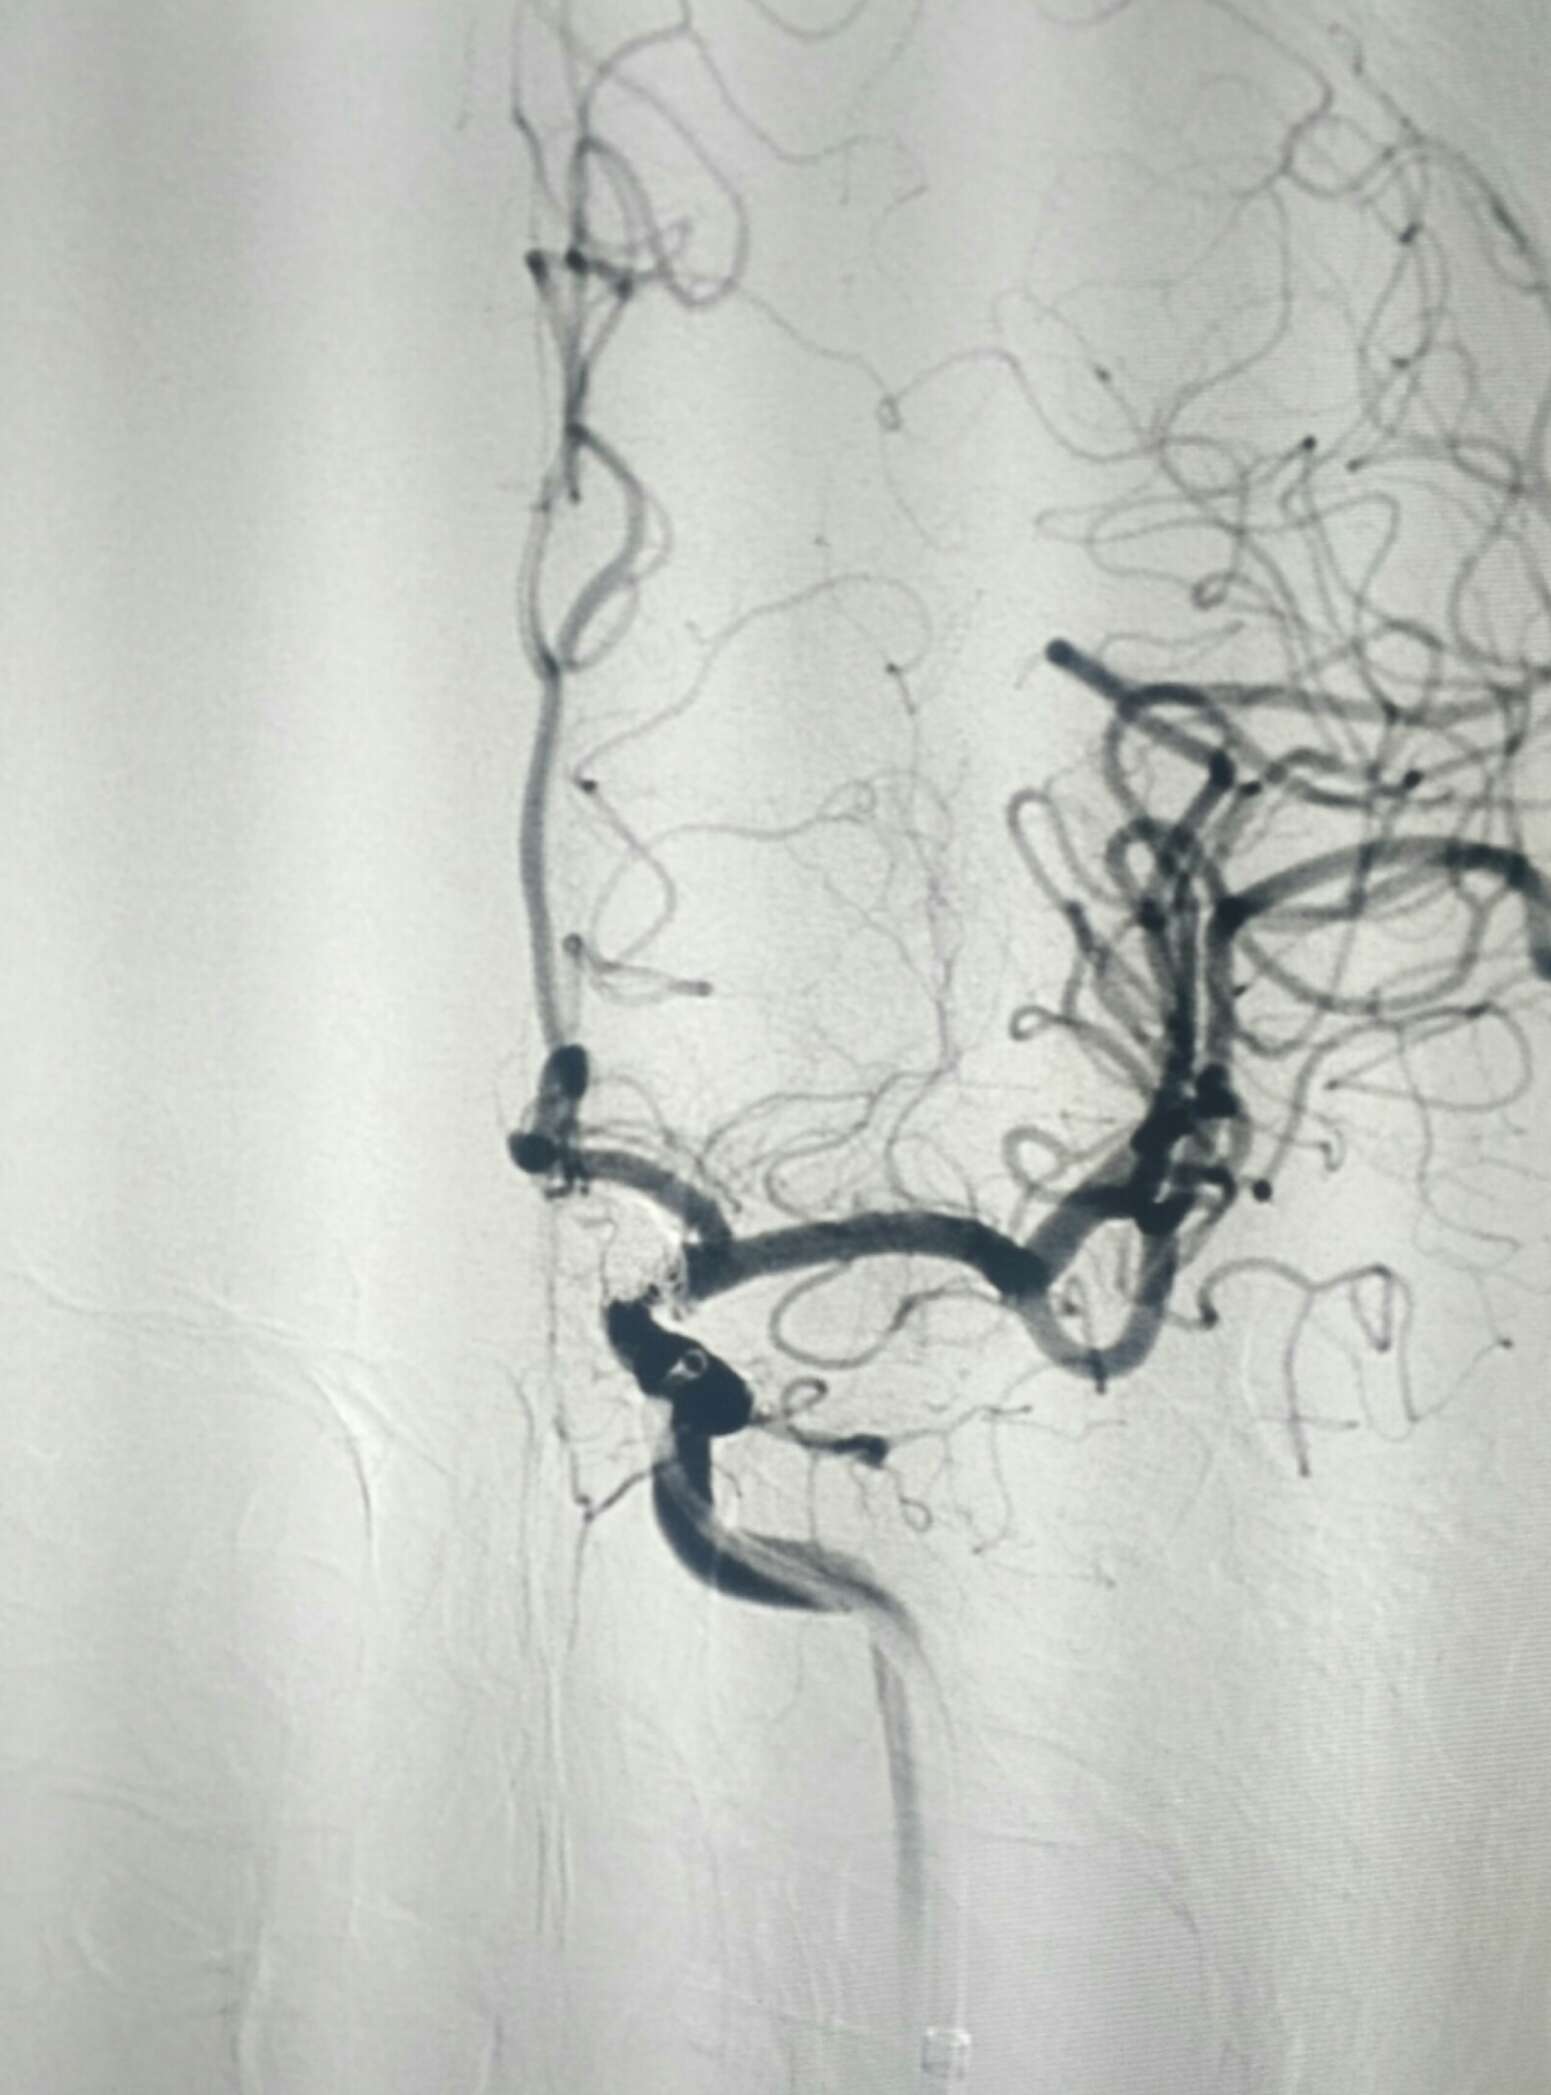

术后20天复查造影动脉瘤栓塞良好无复发显影。目前四肢活动正常,不完全运动性失语,继续康复!

侧位

显示支架

复查3D

百花丛中有其身